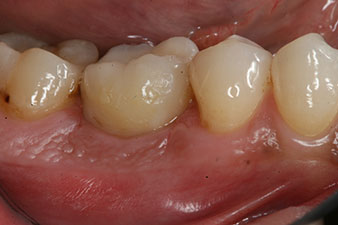

Después de la cicatrización de los tejidos blandos, se volvió a determinar la estabilidad del implante antes de continuar con el tratamiento protésico.

Los dos valores eran prácticamente idénticos y se encontraban en la transición del área media a la alta; en este punto cabe reseñar que el valor más bajo sirve siempre como referencia para establecer el tratamiento adecuado.

Con ello, fue posible documentar una correcta osteointegración y una estabilidad biológica suficiente, lo que permitió realizar una conformación en la misma sesión.

Las figuras finales muestran la corona de composite monolítica atornillada in situ y la radiografía de control (figuras 9 y 10) (6).